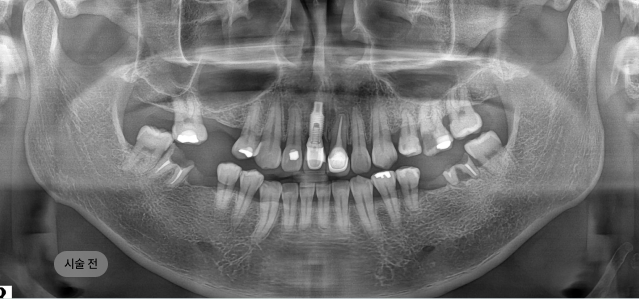

화면을 드래그하여 전/후를 비교해 보세요